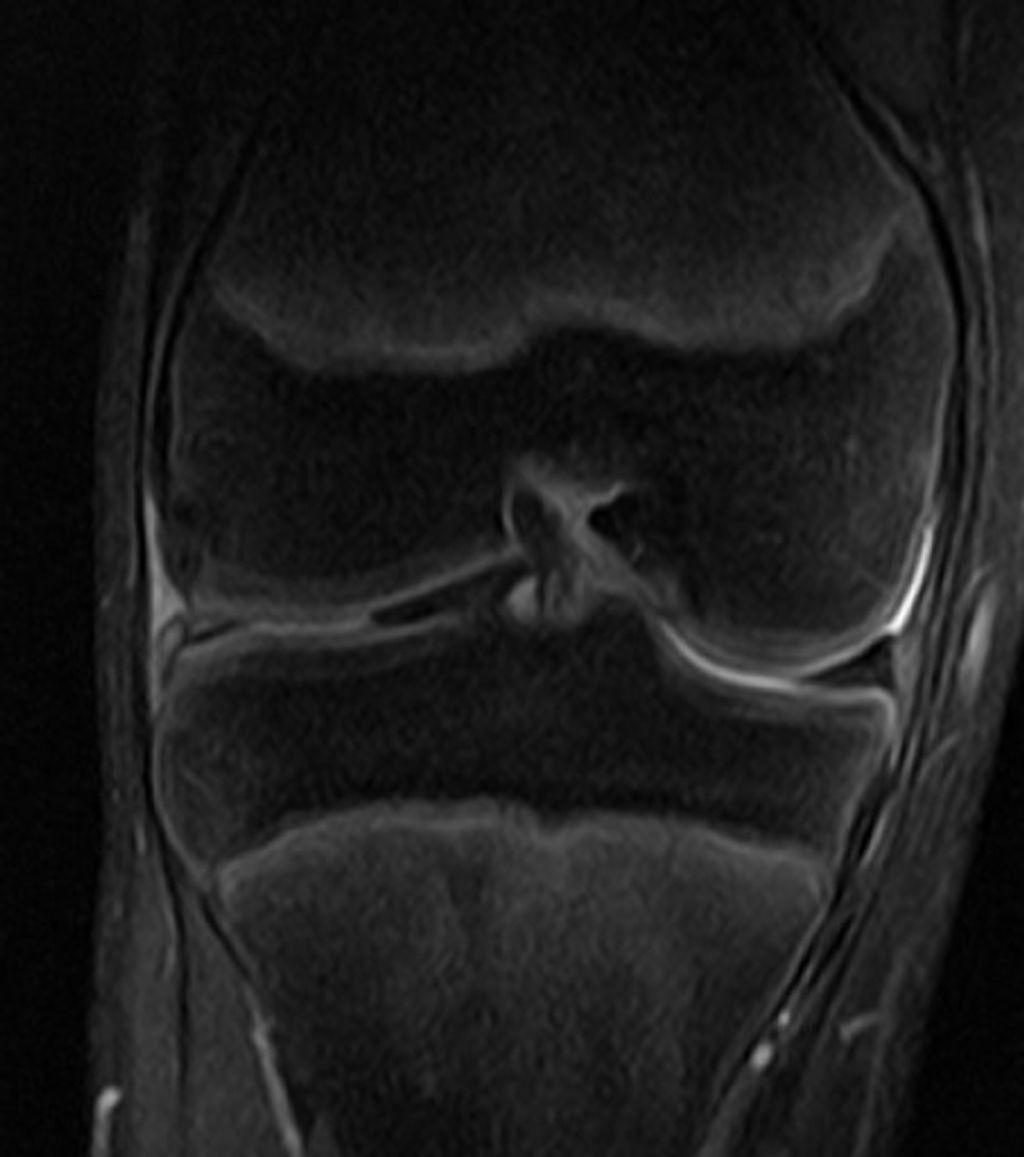

Imaging Techniques

In our quest to accurately diagnose meniscus injuries, we often turn to imaging techniques. These methods provide us with a clear picture of the internal structures of the knee, allowing us to assess the extent of the injury. Magnetic Resonance Imaging (MRI) is the gold standard for visualizing meniscus tears due to its high sensitivity and specificity. However, we also consider other modalities such as ultrasound and X-rays, particularly when MRI is contraindicated or unavailable.

Ultrasound is advantageous for its real-time imaging capabilities, which can be particularly useful in dynamic assessments. X-rays, while not as detailed for soft tissue injuries, can help rule out other conditions such as fractures or osteoarthritis. It’s important to note that while imaging provides valuable information, it should be interpreted in conjunction with clinical findings.

Tip: Always correlate imaging results with physical examination findings to ensure a comprehensive assessment of the meniscus injury.